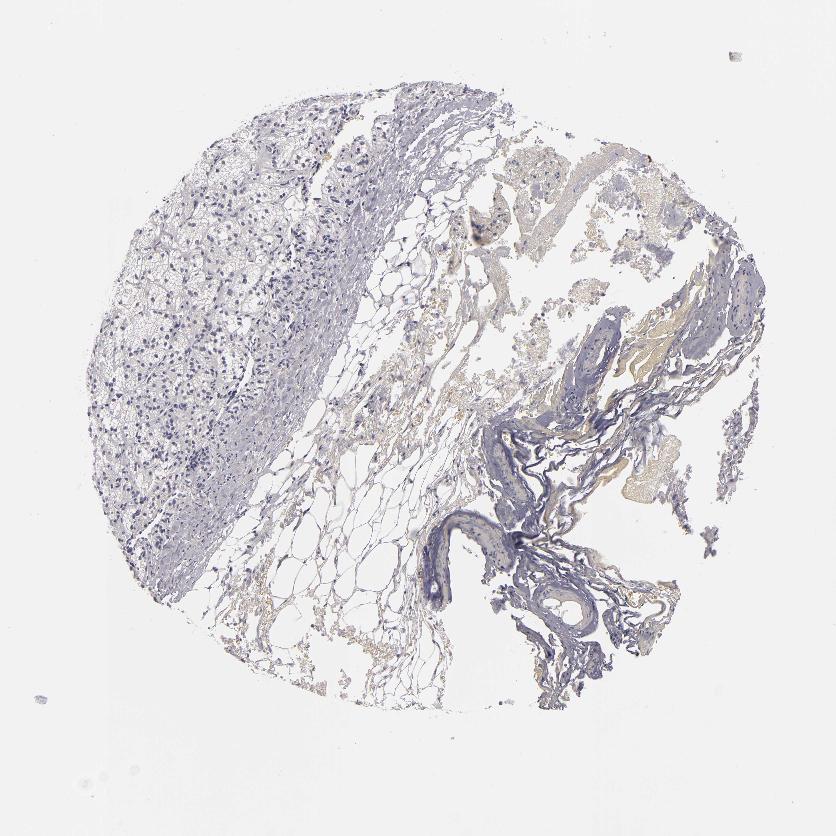

ADRENAL GLAND - Antibody stainingi

Antibody staining in the annotated cell types in the current human tissue is reported as not detected, low, medium, or high, based on conventional immunohistochemistry profiling in selected tissues. This score is based on the combination of the staining intensity and fraction of stained cells.

Each image is clickable and will lead to virtual microscopy that enables deeper exploration of all samples and also displays staining intensity scores, fraction scores and subcellular localization as well as patient and tissue information for each sample.

Antibody HPA044848Antibody HPA056897Antibody CAB002450

Glandular cells Not detectedNot detectedNot detected